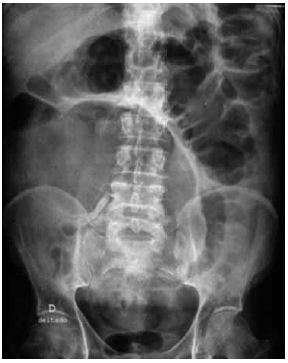

Homem, 70 anos, apresenta tumor no cólon esquerdo e está fazendo exames de estadiamento e avaliação pré-operatória. O exame de colonoscopia completo não revelou lesões sincrônicas. Aguardando ser novamente atendido, começou a apresentar dor abdominal e distensão importante do abdome, com parada de eliminação de gases e fezes. Procurou o pronto-socorro, sendo que lhe foi solicitada uma radiografia do abdome (VIDE IMAGEM).